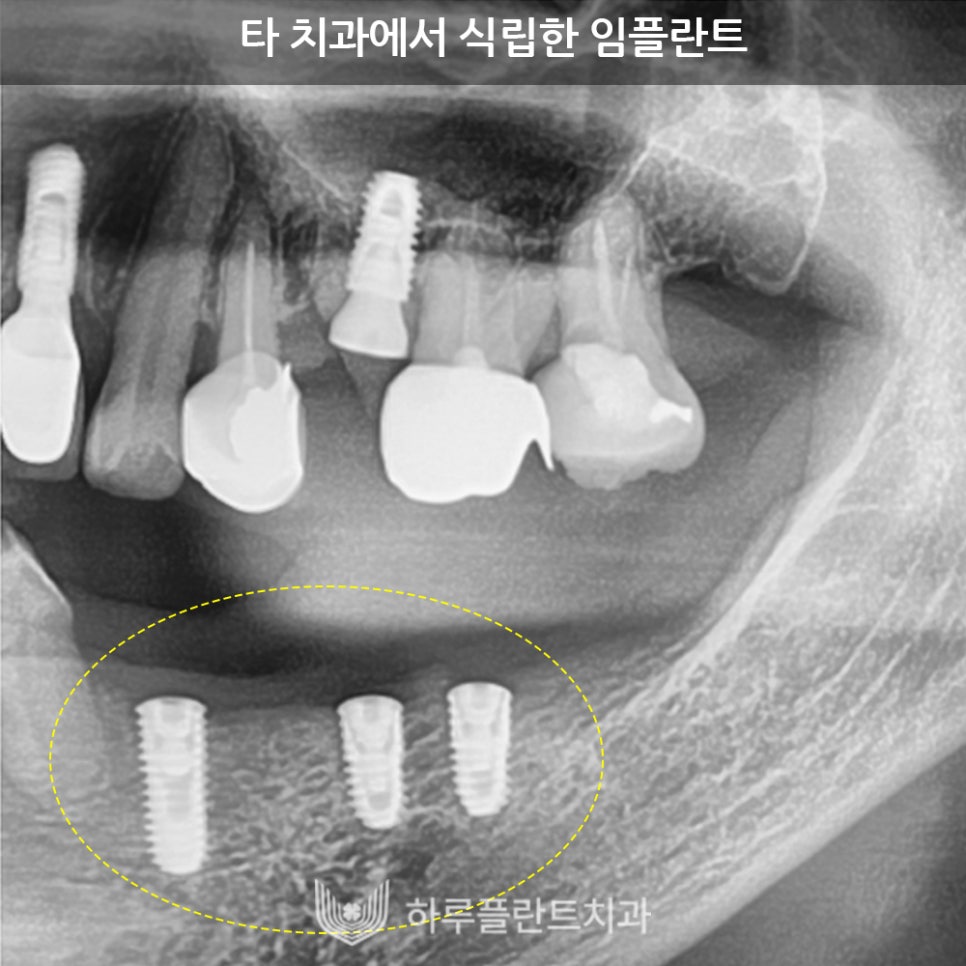

위 사진은 타치과에서 몇 개월 전

임플란트 식립 후 건강상, 거리상의 이유로

본원에서 치료를 마무리하러

내원하신 분의 엑스레이 사진입니다.

2차 수술을 진행하기 위해 잇몸을 열었습니다.

임플란트 뿌리에 보철물을 연결하는 과정인데요.

아직 보철도 연결하지 않은 상태인데

이미 임플란트 상부가

잇몸뼈 밖으로 노출된 모습입니다.

수술 당시에는 얇은 뼈에 의해 덮여있던

임플란트가 불과 수개월 사이에

뼈가 흡수되며 노출된 것입니다.

이렇게 픽스처 주위 상부 잇몸뼈가 흡수되어

외부로 노출되면

세균에 의한 임플란트 주위염에

매우 취약한 상태가 됩니다.

임플란트를 세균으로부터 보호하기 위해

최소 1.5mm 두께의 잇몸뼈로 덮어

보호해 주어야 오랫동안 염증이 발생하지 않고

견딜 수 있는 구조입니다.

이것이 첫 번째 전제가 되어야

성공적으로 임플란트를 식립할 수 있습니다.